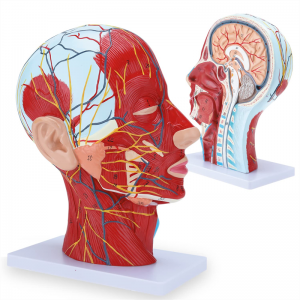

| ਫੀਚਰ | ਮਾਡਲ ਸਿਰ ਅਤੇ ਗਰਦਨ ਦੇ ਅੰਦਰੂਨੀ ਅਤੇ ਬਾਹਰੀ ਪਾਸਿਆਂ ਦੇ ਅੰਦਰੂਨੀ ਰੂਪਨ ਵਿਗਿਆਨ ਦੇ ਨਾਲ-ਨਾਲ ਖੂਨ ਦੀਆਂ ਨਾੜੀਆਂ ਅਤੇ ਨਾੜਾਂ ਦੇ structures ਾਂਚਿਆਂ ਦਾ ਸਥਾਨਕ ਰੂਪ ਵਿਗਿਆਨ ਦਰਸਾਉਂਦਾ ਹੈ, ਅਤੇ ਇੱਥੇ 84 ਹਿੱਸੇ ਹਨ ਜੋ ਕੁੱਲ ਵਿੱਚ ਸੰਕੇਤ ਦਰਸਾਉਂਦੇ ਹਨ. |

【ਸਤਹੀ ਨਿ ur ਰੋਵਸਕੂਲਰ ਮਾਸਪੇਸ਼ੀ ਦਾ ਮਾਡਲ】 ਉੱਚਿਤ ਵਿਸਥਾਰਪੂਰਕ, ਨੰਬਰ ਮਾਰਕ ਕੀਤੇ, ਕੰਬਦੇ ਕੰ the ੇ, ਨਾੜੀ ਅਤੇ ਗਰਦਨ ਦੇ ਅੰਦਰੂਨੀ structures ਾਂਚਿਆਂ ਦੀ ਸਮਝ ਨੂੰ ਡੂੰਘਾ ਕਰੋ. ਲਾਲ-ਧਮਣੀ, ਨੀਲੀ-ਨਾੜੀ, ਪੀਲੇ-ਨਸ.

【ਵਿਸ਼ੇਸ਼ਤਾਵਾਂ】 ਦਾ ਸਾਹਮਣਾ ਕੀਤੇ ਚਿਹਰੇ ਦੀਆਂ ਸਤਹੀ ਮਾਸਪੇਸ਼ੀਆਂ ਨੂੰ ਦਰਸਾਉਂਦਾ ਹੈ; ਸਤਹੀ ਖੂਨ ਦੀਆਂ ਨਾੜੀਆਂ ਅਤੇ ਚਿਹਰੇ ਦੀਆਂ ਨਾੜੀਆਂ ਅਤੇ ਖੋਪੜੀ; ਪੈਟੀਡ ਗਲੈਂਡ ਅਤੇ ਵੱਡੇ ਸਾਹ ਦੀ ਨਾਲੀ ਦੇ ਅੰਦਰੂਨੀ structures ਾਂਚਿਆਂ; ਸਰਵਾਈਕਲ ਰੀੜ੍ਹ ਦੀ ਸੋਗਿਤਲ ਕਰਾਸ-ਸੈਕਸ਼ਨ structure ਾਂਚਾ.

ਇਹ ਮਾਡਲ ਮਨੁੱਖ ਦੇ ਸੱਜੇ ਸਿਰ ਅਤੇ ਮਨੁੱਖ ਦੇ ਮੱਧ ਸੇਂਟਟਲ ਭਾਗ ਦਾ ਵੇਰਵਾ ਦਰਸਾਉਂਦਾ ਹੈ. ਸਤਹੀ ਵੀ ਸ਼ਾਮਲ ਹੈ

ਖੁੱਲੇ ਚਿਹਰੇ ਦੇ ਮਾਸਪੇਸ਼ੀ; ਸਤਹੀ ਖੂਨ ਦੀਆਂ ਨਾੜੀਆਂ ਅਤੇ ਚਿਹਰੇ ਅਤੇ ਖੋਪੜੀ ਦੀਆਂ ਨਾੜੀਆਂ; ਅੰਦਰੂਨੀ structures ਾਂਚਿਆਂ

ਪੈਟੀਡ ਗਲੈਂਡ ਅਤੇ ਉਪਰਲੇ ਸਾਹ ਦੀ ਨਾਲੀ; ਸਰਵਾਈਕਲ ਰੀੜ੍ਹ ਦੀ ਸੋਗਿਤਲ ਕਰਾਸ-ਸੈਕਸ਼ਨ structure ਾਂਚਾ.

ਮਾਡਲ ਨੇ ਸਿਰ ਅਤੇ ਗਰਦਨ ਅਤੇ ਗਰਦਨ ਦੇ ਮੱਧਮ ਅਤੇ ਪਾਰਦਰਸ਼ੀ ਸਮੂਹਾਂ ਅਤੇ ਇਸ ਦੇ ਨਾੜੀ ਅਤੇ ਨਸਾਂ ਦੇ structures ਾਂਚਿਆਂ ਅਤੇ ਨਸਾਂ ਦੇ structures ਾਂਚਿਆਂ ਦਾ ਸਥਾਨਕ ਰੂਪ ਵਿਗਿਆਨ ਅਤੇ ਇਸ ਦੇ ਨਾੜੀ ਅਤੇ ਨਸਾਂ ਦੇ structures ਾਂਚਿਆਂ ਦਾ) ਕੁੱਲ 100 ਸਾਈਟ ਸੂਚਕਾਂ ਦੇ ਨਾਲ ਦਿਖਾਇਆ ਗਿਆ ਹੈ.

ਇਹ ਮਾਡਲ ਇੱਕ ਕੁਦਰਤੀ ਵੱਡਾ ਸਿਰ ਅਤੇ ਗਰਦਨ ਸਤਹੀ ਨਿ ur ਰੋਵਸਕੁਲਰ ਮਾਸਪੇਸ਼ੀ ਮਾਡਲ, 1 ਕੰਪੋਨੈਂਟ, ਚਿਹਰੇ ਅਤੇ ਖੋਪੜੀਆਂ ਦੇ ਸਤਹੀ ਮਾਸਪੇਸ਼ੀਆਂ ਦੇ ਵੇਰਵੇ ਦਿਖਾਉਂਦੇ ਹੋਏ, ਨਸਾਂ ਅਤੇ ਪੈਰੋਟਿਡ ਗਲੈਂਡ ਅਤੇ ਵੱਡੇ ਸਾਹ ਦੀ ਨਾਲੀ ਦਾ ਮੈਡੀਅਲ ਬਣਤਰ, ਅਤੇ ਸਰਵਾਈਕਲ ਰੀੜ੍ਹ ਦੀ ਸੋਗਟਲ ਸੈਕਸ਼ਨ ਦਾ structure ਾਂਚਾ